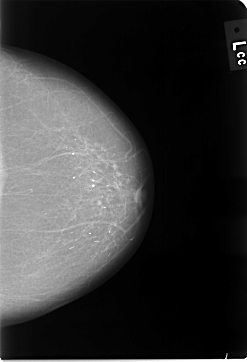

C_0011_1.LEFT_CC

LEFT_CC LINES 5784 PIXELS_PER_LINE 3952 BITS_PER_PIXEL 12 RESOLUTION 50 NON_OVERLAY